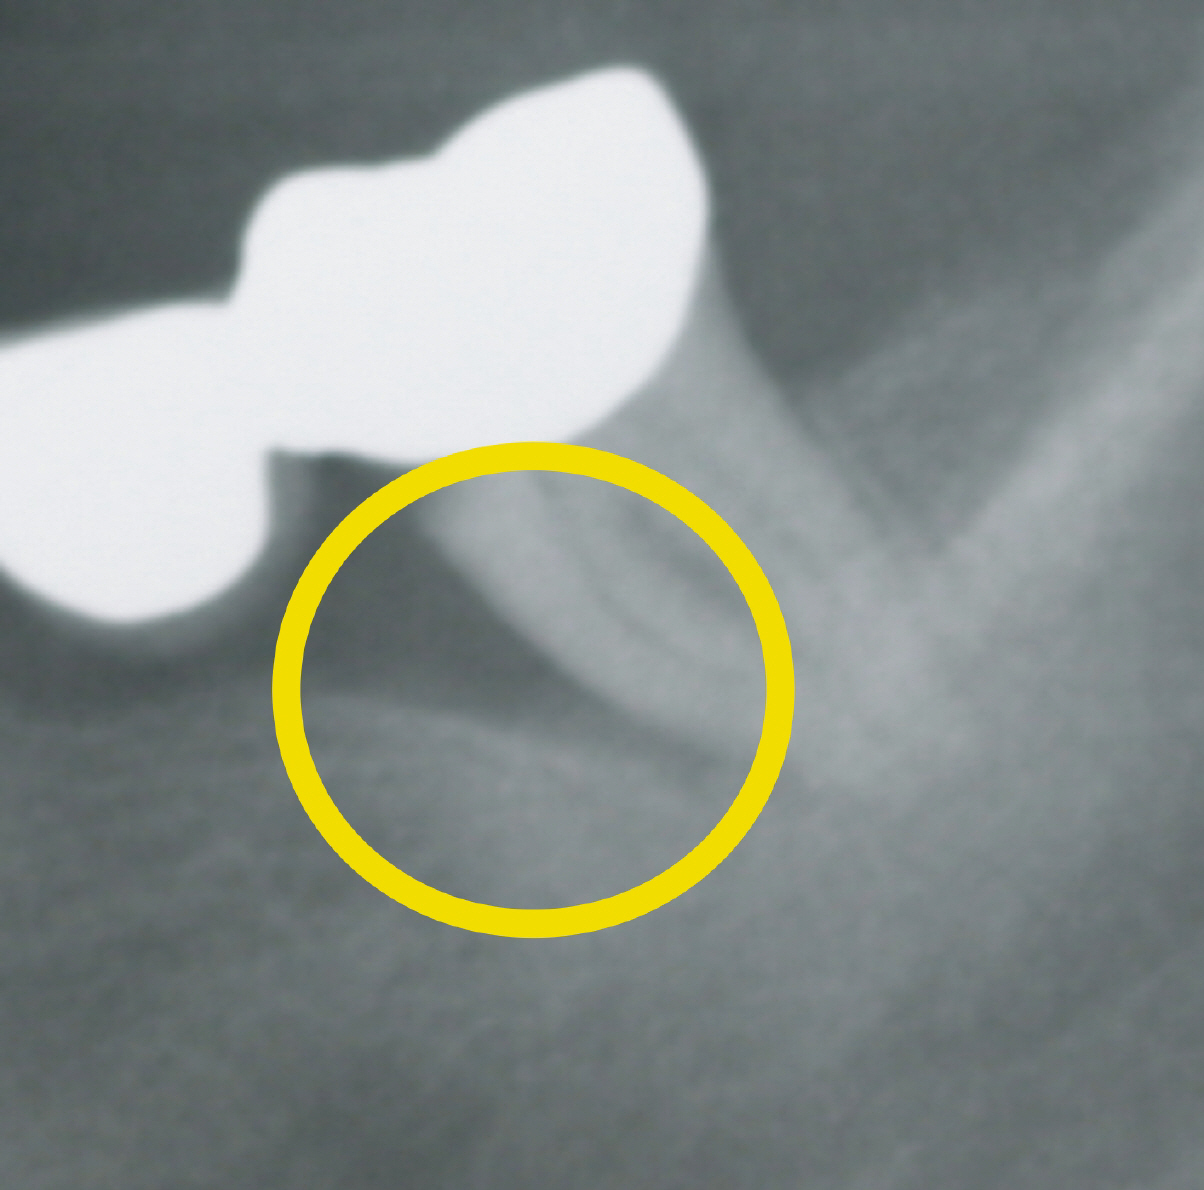

Vorsicht Tasche!

Das Röntgenbild zeigt den massiven Knochenverlust als schwarze Lücke.

Parodontose wird durch Mikrobakterien in den Zahnfleischtaschen verursacht, die eine Entzündung des Zahnhalteapparates und des umliegenden Knochens verursachen. Sie ist von großer aktueller Bedeutung, denn mehr als zwei von drei Menschen leiden beispielsweise an einer Zahnfleischerkrankung, die nicht nur häufig zum Zahnverlust führt, sondern daneben auch der größte einzelne Risikofaktor für koronare Herzerkrankungen ist und unsere Gesamtgesundheit schädigt.